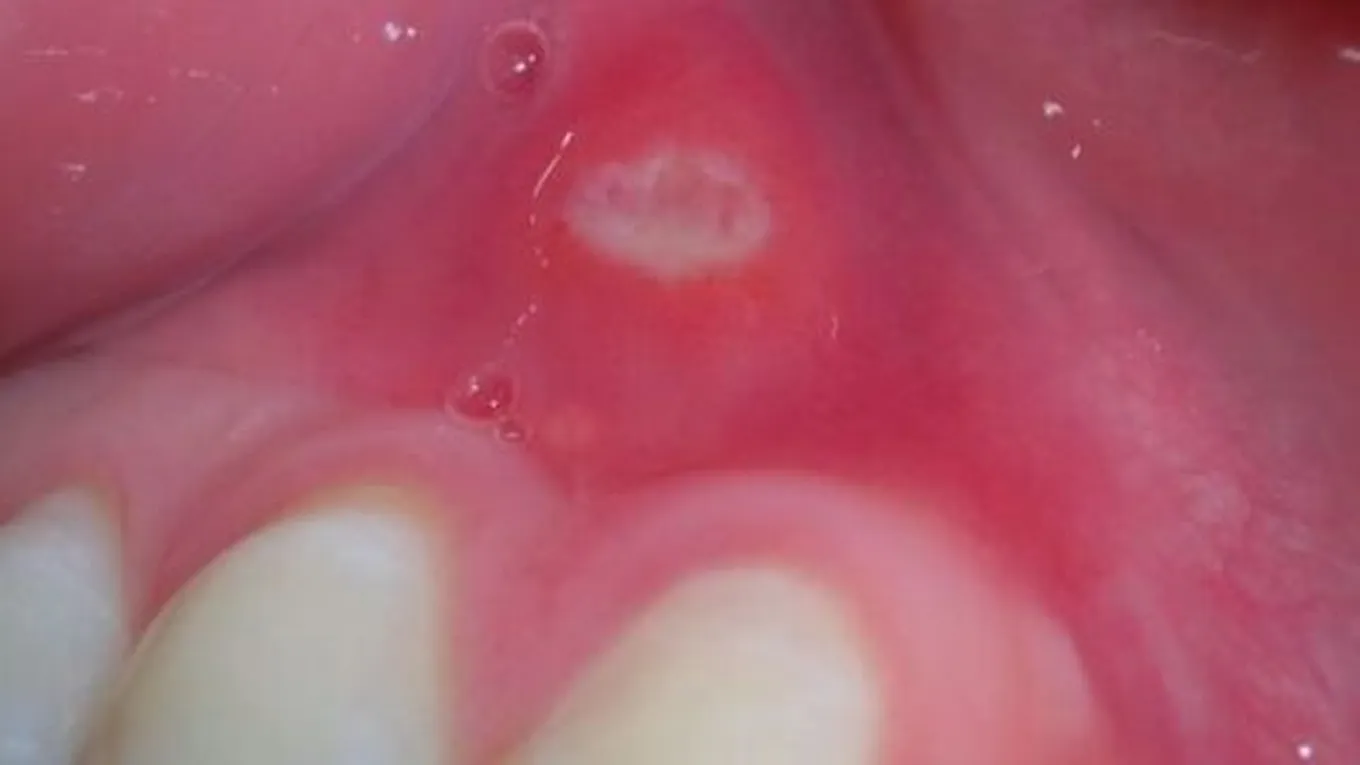

ظهور حبة بيضاء في اللثة

تعتبر حبوب اللثة من الأمور الطبيعية التي يتعرض لها الكثير من الأشخاص، فهو أمر طبيعي وغير مقلق، ولا يعدّ مرضاً، ولكن في كثير من الأحيان يسبب ظهورها الشعور بعدم الراحة، وقد تسبب ألماً وحرقة عند تناول الشراب أو الطعام، وتختلف أماكن ظهورها في الفم مثل: اللثة، والحنك، واللسان، والشفتين، وفي هذا المقال سنتعرّف على أسباب ظهور حبّة بيضاء في اللثة، مع ذكر بعض الطرق الطبيعيّة لإزالتها.